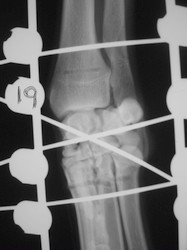

PRÁCTICAS CURSO DE FIJACIÓN EXTERNA PERFECCIONAMIENTO.

Artrodesis carpo.